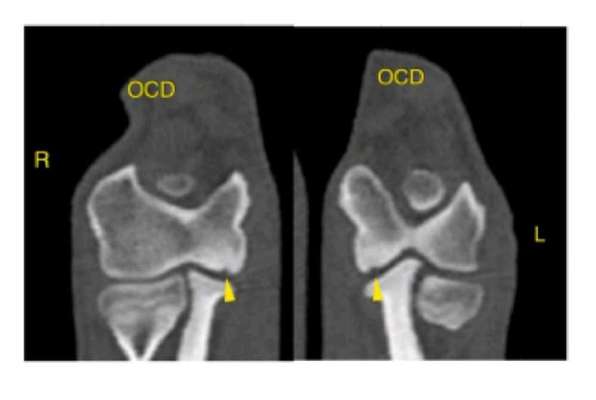

Hallo liebe Leute, Aufgrund mehrwöchiger Lahmheit vorne links bei unserem 6 Monatigen Hund (Japanspitz, eher kleine - mittelgroße Rasse) haben wir in einer Tierklinik ihn röntgen lassen und anschließend ins CT gegeben. Nun hat er laut Ärzten im Ellenbogen eine beidseitige OCD und soll zumindest auf der linken Seite operiert werden. Wir sind recht überfordert mit der Diagnose und wollen eine 2. Meinung noch einholen. Angehängt sind die Bilder. Unser Hund hatte keine Unfälle (natürlich ist er mal im Laufen auf glatten Boden daheim mal weggerutscht). Gassi sind wir immer nach der 5-10 Minutenregel pro Monat gegangen. Treppen wurde und wird er getragen. Kein wildes Spiel mit anderen Hunden. Er darf nicht allein auf die Couch. Essen bekam er Anfangs das HappyDog für Welpen, ab und zu bisschen Naturjoghurt und Buttermilch. Seit einer ganzen Weile erhält er aber nun das Welpenfutter mit Lamm von Tails and Tales. Das frisst er ohne Joghurt (das vorherige TroFu wollte er kaum noch essen, daher der Wechsel). Leckerlis bestehen, wenn, aus seinem Trockenfutter, weil er das sehr gern mag. Oder getrocknetes Lamm oder Pferd. Weil er vor einer Weile Giardien hatte bekommt er noch was zum Aufbau der gesunden Darmflora und hat inzwischen wieder guten Stuhlgang etc. Das Lahmen schwankt übrigens. Jetzt läuft er seit 2 Tagen recht gut ( Gassi ist schon seit Wochen nur an der Leine), aber das muss nichts heißen. In seiner Zuchtstätte gab es seit 20 Jahren nicht so einen Fall und ich glaube das auch. Sind hier Experten für OCD? Was habt ihr für Erfahrungen? Was sagt ihr zu unserem Befund? Macht eine OP Sinn in diesem Fall? LG Anna

Upps, das Röntgenbild ist krass!

Es kommt gelegentlich (selten) auch beim Belgier vor. Beidseitig eher selten.

So wie das Bild aussieht muss operiert werden und das relativ schnell.